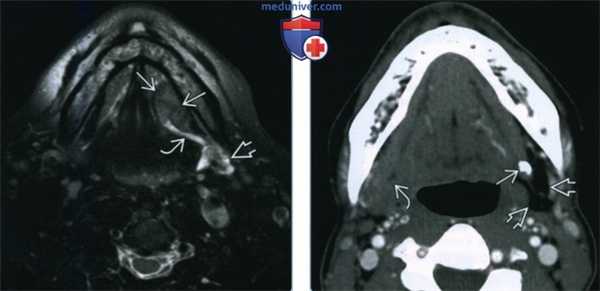

(Слева) MPT T2BИ FS, аксиальная проекция, округлое образование с четкими контурами у пациента с раком дна полости рта. Опухоль блокирует проток левой поднижнечелюстной железы, что ведет к ее вторичному воспалению. Сигнал от железы гиперинтенсивный.

(Справа) КТ с КУ, аксиальная проекция, срез на уровне дна полости рта у пациента с «новообразованием» правой поднижнечелюстной области. В проксимальной части, вблизи ворот левой поднижнечелюстной железы, виден крупный конкремент. Обратите внимание на выраженную жировую атрофию слева с формированием хронического сиаладенит. «Опухоль» с правой стороны оказалась просто здоровой железой.